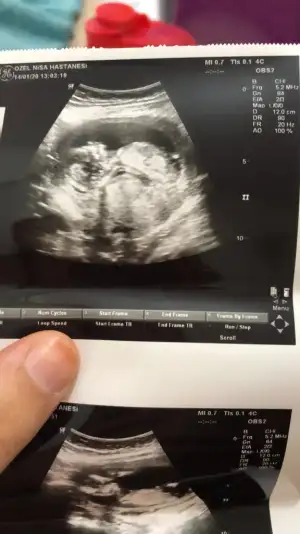

11 yada 12 olmalıMerhabalar, benimkine de bakabilirseniz çok sevinirim, burada 10. Haftanın içinde idi...

Net degil 11+ yada 12 hafta paylşın10+ 5 gunluk.yuzu bize donuk sekilde.acaba tahmin yapan varmi

usgde bakarken cikintiyi uzun ve net gordum hatta dikceydi.bacaklari acik yuzu bana donuk kafasini oynatiyordu.ama fotolarda net belli degil..belki anlarsiniz diye dusundum.yinede tsklerNet degil 11+ yada 12 hafta paylşın

O haftalarda nub iki tarafa benzer en iyi nub 12 haftausgde bakarken cikintiyi uzun ve net gordum hatta dikceydi.bacaklari acik yuzu bana donuk kafasini oynatiyordu.ama fotolarda net belli degil..belki anlarsiniz diye dusundum.yinede tskler